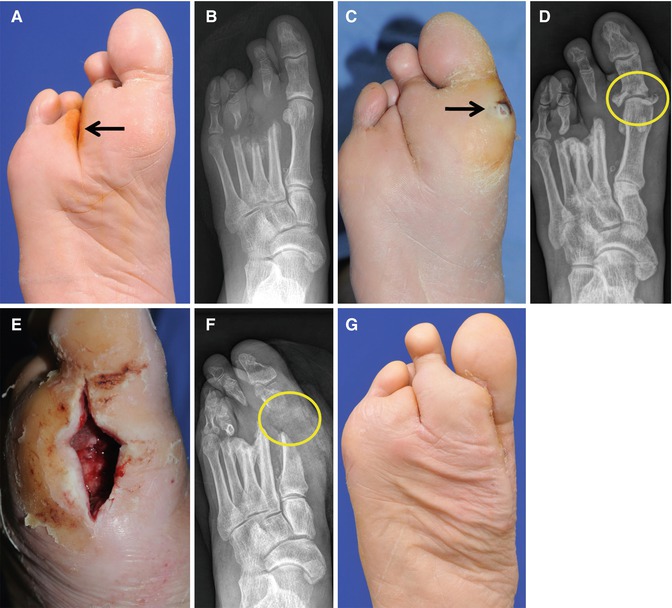

It is important to educate the patients in foot care guidelines. (A–C) A large, infected plantar ulcer has been successfully treated. (D) One month after the healing, new pre-ulcerative lesions (arrows) developed by the indifference to the pressure off-loading

(A, B) A plantar ulcer previously healed successfully (an arrow). (C, D) After 6 months, a new lesion was developed (an arrow) due to pressure injury. Even though the wound did not show evidence of infection, deep tissue infection including osteomyelitis was demonstrated in a plain radiograph (a circle). (E, F) The infected tissues were surgically debrided (a circle). (G) A view after healing